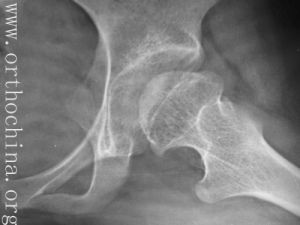

孩子跛行後,一般情況下如果損傷不嚴重,是可以自愈的。但有時跛行也可能潛伏著其他疾病,所以需要及時的治療,以免造成永久性的殘疾。起病緩慢,病程長。患兒數月來出現間歇性跛行與疼痛,疼痛常向膝部、大腿內側放射。症狀可因活動而加重,休息後緩解。部分病兒早期可無症狀或僅有輕微症狀,有時只有輕微步態異常,如行走時小腿內鏇。典型體徵為患髓有輕度屈曲內收畸形,伸直時,外展和內鏇受限。鏇轉髖關節時,有輕度肌肉痙攣。該病於活動期,症狀較明顯。約20%病例有外傷史,傷後急性發病,有破行,髖關節疼痛及活動受限,患肢短縮。通常伴有肌痙攣,以內收肌和髂腰肌最顯著。大腿及臀部肌肉有廢用性萎縮,髖關節活動受限,多為屈髖、外展外鏇動作,即“4”字試驗陽性。有時會出現固定的屈曲內收畸形。臨床上有三個重要體徵,即肥胖、髖關節活動範圍減小和內收肌痙攣。本病至晚期,症狀逐漸緩解,以至於消失。關節活動可恢復正常,或僅留外展和鏇轉活動受限和大粗隆膨突。臨床表現不一定與x線所見一致,有時在x線片上顯示股骨頭明顯畸形但症狀很輕,甚至無症狀,這可能表明髖臼對畸形的股骨頭已相適應。

早期診斷非常重要,對4一10歲兒童,凡不明原因的破、膝部疼痛與被行,病兒身材矮小,有反覆發作病史;早期x線片見到股骨頭內下緣至髖臼下緣的“淚滴”的距離增寬超過2mm,應按觀察髖處理,讓患兒3—6月內定期來門診由專科醫師隨訪檢查,直至除外Perthes病為止。拍攝高質量x線片是早期診斷該病不可缺少的條件,近年來有人使用同位素掃描對本病早期診斷,若有骨壞死,局部缺血區可出現所謂冷區,修復期血管增生,有新骨形成,就出現核素密集,出現所謂熱區,與健側比較,可測知股骨頭的供血狀態。這方面比一般x線片檢查所獲得的陽性徵要早2—5個月。其確診率高達95%。